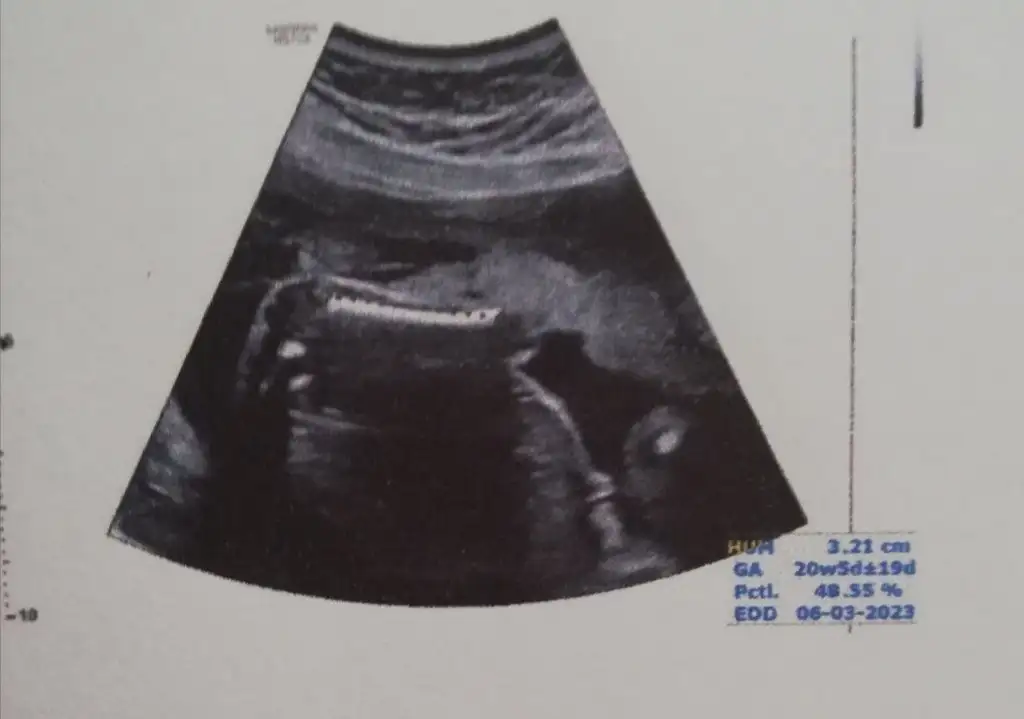

Ayrıntılı ultrasonumuz bitti, yaklaşık 45 dk sürdü. Minnoş zorluk çıkarmadı kıpır kıpırdı her yerini gösterdi.Çok şükür bir sorun çıkmadı her şey olması gerektiği gibi. Normal doğuma engel teşkil edilecek bir şey de görülmüyor. Bebek haftası ile uyumlu 340 gr. Olmuş. Eli hep ağzında emiyordu, doktor zor çıkarttırdı. Doğum için 1 mart ve sonrasını bekliyoruz dedi maksimum 9 mart. Amniyon sıvısı, plasenta, kan akışı, boy, kg, organlar her şey iyi. Bu da minik tosuncuk kızım